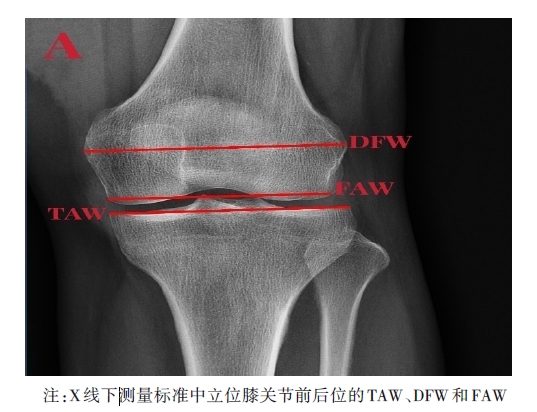

目的 测量X线下胫骨平台与股骨远端的解剖学关系,并评估Schatzker IV-C胫骨平台骨折术中平台宽度复位情况对术后临床疗效的影响。 方法 2012年8月至2022年8月,在我院收集207例标准中立位正常成年人膝关节X线(未骨折组)及60例Schatzker IV-C型骨折患者术前及术后即刻膝关节前后位X线(骨折组)。分别测量两组胫骨近端关节宽度(TAW)、股骨远端髁宽度(DFW)及股骨远端关节宽度(FAW),计算TAW/DFW和TAW/FAW比值,定义骨折组术后即刻X线TAW介于FAW与DFW之间为复位良好组,反之为复位不良组,并在术后1年对两组进行膝关节美国特种外科医院评分(HSS)。 结果 在未骨折组中,TAW/DFW和TAW/FAW比值无明显性别或侧别差异(P > 0.05),而骨折组术前与未骨折组TAW/DFW和TAW/FAW比值差异有统计学意义(P < 0.05)。骨折组中复位良好组与复位不良组的术后1年HSS评分比较差异有统计学意义(P < 0.05)。 结论 正常成年人胫骨平台与股骨远端的X线下解剖学关系相对恒定,可为Schatzker IV-C骨折术中平台宽度复位提供影像学参考,若术后复位后X线TAW/DFW> 1或TAW/FAW < 1提示复位不佳,则预示术后膝关节功能恢复不良。

Objective To investigate the radiographic anatomical relationship between tibial plateau and distal femur and evaluate the impact of reset tibial plateau of various widths after reduction of the Schatzker IV-C tibial plateau fractures on postoperative outcomes. Methods We collected and reviewed the X-ray images of the normal knees of 207 standard neutrally-positioned adults (non-fracture group) and pre-and post-operative immediate anterior-posterior X-ray images of the knees of 60 patients with Schatzker IV-C fractures (fracture group) in our hospital from August 2012 to August 2022. We measured the proximal tibial joint width (TAW), distal femoral width (DFW), and distal femoral joint width (FAW) in both groups and calculated the TAW/DFW and TAW/FAW ratios. In the fracture group, the cases with TAW between FAW and DFW were assigned to the well-reduced group, while those with TAW outside this range between FAW and DFW to the poorly-reduced group. Both groups were assessed using the Hospital for Special Surgery knee score (HSS) one year after operation. Results In the non-fracture group, there were no significant differences in gender or affected side in terms of TAW/DFW and TAW/FAW ratios (P > 0.05), while in the fracture group, there were statistically significant differences in the TAW/DFW and TAW/FAW ratios compared to the non-fracture group (P < 0.05). There was a statistically significant difference in the one-year postoperative HSS scores between the well-reduced and poorly-reduced groups in the fracture group (P < 0.05). Conclusion The radiographic anatomical relationship between the tibial plateau and distal femur in normal adults is relatively constant, providing a radiological reference for resetting the tibial plateau to a satisfactory width during reduction of Schatzker IV-C fractures. TAW/DFW > 1 or TAW/FAW < 1 indicates a poor reduction of the fracture and predicts poor postoperative recovery of knee joint function.